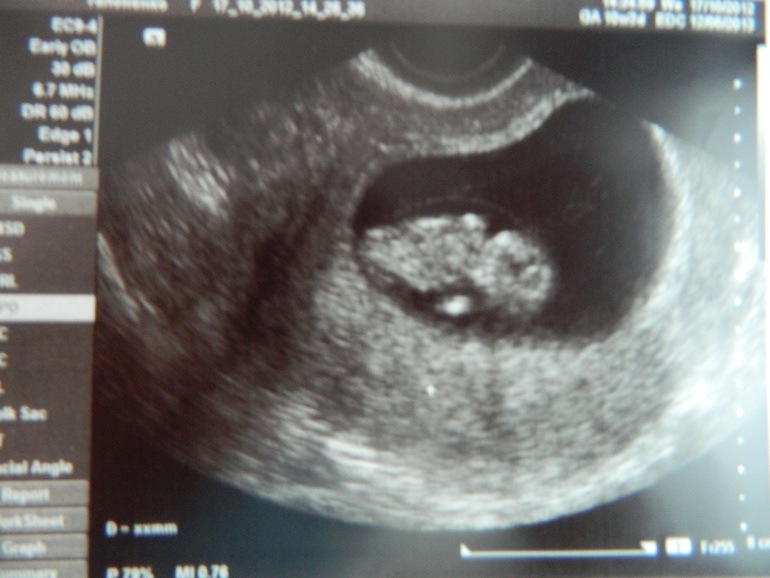

А вот это 3д и 2 д фотки моей крошечки в 10 недель беременности (по-моему самое трогательно, когда там еще вообще бусинка)